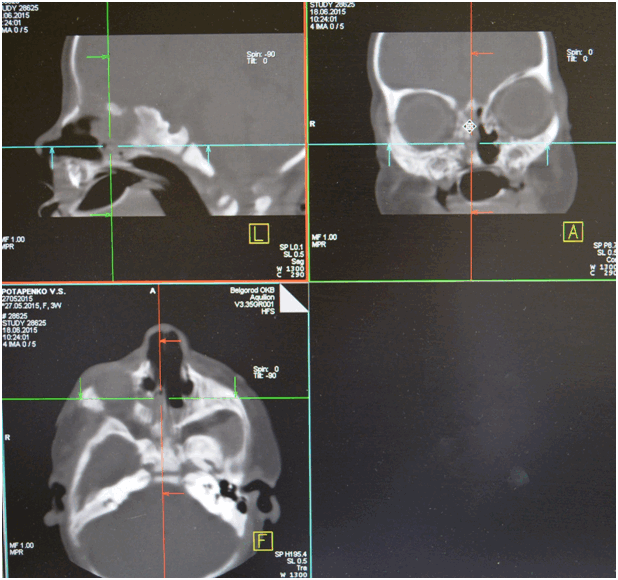

Необходимо провести компьютерную томографию, так как она даст информацию о сопутствующих изменениях полости носа. Это позволит провести операцию по восстановлению просвета хоаны с учетом всех анатомических особенностей.

Для диагностики атрезии хоан используют разные методы: зондирование полости носа, рентгендиагностика с контрастным веществом. В настоящее время широкое применение получила компьютерная томография придаточных пазух носа. Двусторонние полные или частичные атрезии диагностируют у новорожденных и у детей раннего возраста. Односторонние частичные же атрезии хоан могут быть диагностированы и в более позднем возрасте, связано это с тем, что при таких атрезиях носовое дыхание лишь затруднено, а с одной стороны и вовсе не нарушено.

Из анамнеза известно, что указанные жалобы беспокоят с рождения. Ребенок родился в срок 40-41 неделя (27.05.2015), на фоне нарастания дыхательной недостаточности, через два часа после родов проведена интубация трахеи. Экстубация трахеи - 29.05.2015. С 01.06.2015 по 20.06.2015 с диагнозом нижнедолевая сегментарная правосторонняя пневмония, пиодермия, ринит, конъюнктивит девочка была на стационарном лечении в ОГБУЗ "Детской областной клинической больницы" г. Белгород. Проведено СКТ: картина двусторонней атрезии хоан. Рекомендовано консультация в НКЦО г. Москва. Ребёнок консультирован проф. Юнусову А.С. 22.06.2015 г. и направлен на хирургическое лечение в Отдел детской ЛОР патологии ФГБУ НКЦО ФМБА России.